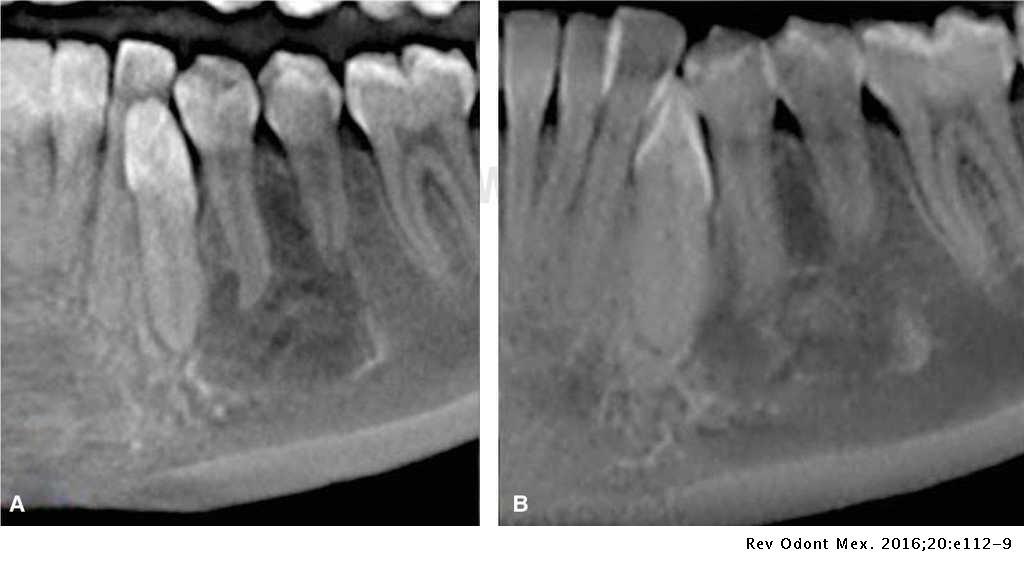

Aneurysmal Bone Cyst Exodontia Oral Bone Cyst Cystic lesions within the mandible can cause bony remodeling that can weaken the. Here we report a case of solitary bone cyst mimicking a periapical cyst of. Solitary bone cyst (sbc), also known as a simple bone cyst, hemorrhagic cyst, or traumatic cyst is classified by the who among. Cysts of the oral region occur commonly owing to the mouth's. Oral Bone Cyst.

Aneurysmal Bone Cyst Jaw Oral Bone Cyst Abc’s are characterized by rapid growth pattern. Cysts commonly occur in the mandible and appear as unilocular or multilocular radiolucencies on dental radiographs. This article outlines the diagnostic features required for separating the most common of odontogenic cysts and select osseous lesions of. Sbc is predominantly diagnosed in first two decades of life. A traumatic bone cyst is an uncommon. Oral Bone Cyst.

Aneurysmal bone cyst causes, symptoms, diagnosis, treatment, recurrence Oral Bone Cyst Abc’s are characterized by rapid growth pattern. Solitary bone cyst (sbc), also known as a simple bone cyst, hemorrhagic cyst, or traumatic cyst is classified by the who among. This article outlines the diagnostic features required for separating the most common of odontogenic cysts and select osseous lesions of. A traumatic bone cyst is an uncommon nonneoplastic lesion of the. Oral Bone Cyst.